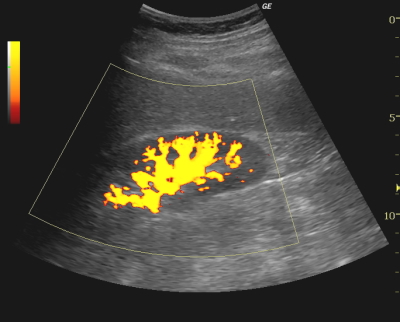

パワードプラ法(PDI:power doppler imaging)

パワードプラ法(PDI:power doppler imaging)は、カラードプラと同様に生体内血行動態に色を付けBモード画像上に重ね合わせながらリアルタイムで表示する方法であるが、パワードプラではドップラー効果で生じるドプラシフトを平均流速で表示するカラードプラとは異なり、信号強度を表示する。従って血流方向の色分けはできないが、低速血流や超音波ビームとの角度が大きいようなカラードプラでは感度の不足となる部位を感度良く表示できる。

近年では非常に高精細なパワー表示、カラー表示も可能になってきており、血管からのはみ出しや滲みが少なく、超低速血流を高精度で表示する技術も進んでいる。